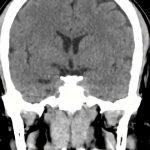

下垂体腺腫

断層撮影

手術前1

手術後

No.’14_52 手術前1

No.’14_52 手術後